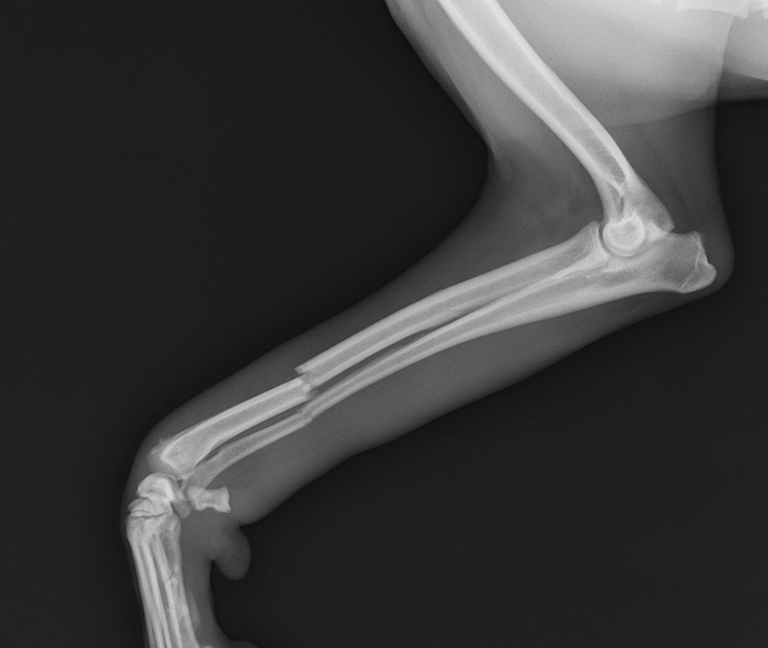

Chirurgies orthopédiques

La chirurgie orthopédique vise à traiter les affections des os, des articulations et des ligaments afin de restaurer la mobilité et de réduire la douleur.

Nous prenons en charge notamment :

- Ligaments croisés (rupture du ligament croisé)

- Prothèses (selon indication)

- Arthroscopie (exploration et traitement mini-invasif de certaines articulations)

- Fractures (stabilisation et réparation)

Dysplasie (hanche/coude)